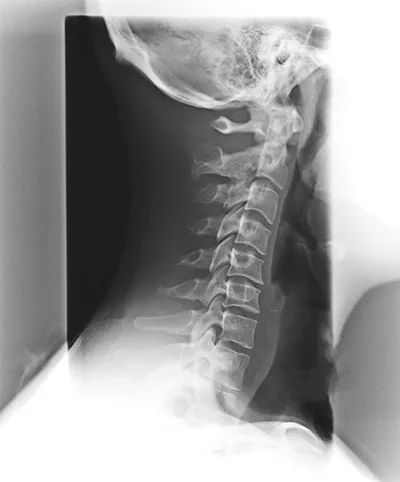

Spinal Degeneration Phase II

Phase II of spinal degeneration introduces stiffness and aches and pains in the spine as the space between the discs decreases further. Most people do not attribute their discomfort to spinal degeneration, but a lack of range of motion may tip them off that something is amiss with their spinal health. If an individual with phase II degeneration seeks chiropractic care, they may never recover full range of motion, but many symptoms of the degeneration can be reversed and most body functions can be restored.